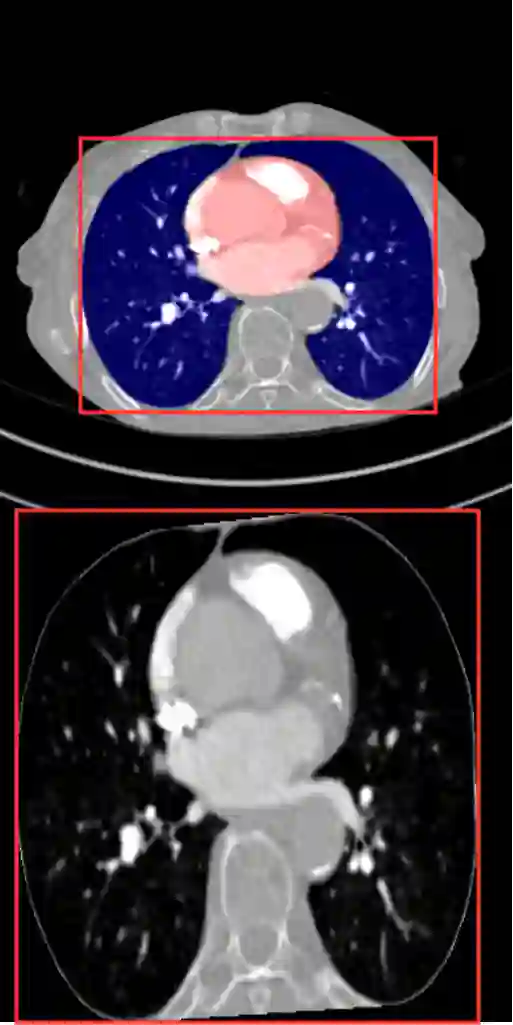

Pulmonary Embolisms (PE) represent a leading cause of cardiovascular death. While medical imaging, through computed tomographic pulmonary angiography (CTPA), represents the gold standard for PE diagnosis, it is still susceptible to misdiagnosis or significant diagnosis delays, which may be fatal for critical cases. Despite the recently demonstrated power of deep learning to bring a significant boost in performance in a wide range of medical imaging tasks, there are still very few published researches on automatic pulmonary embolism detection. Herein we introduce a deep learning based approach, which efficiently combines computer vision and deep neural networks for pulmonary embolism detection in CTPA. Our method features novel improvements along three orthogonal axes: 1) automatic detection of anatomical structures; 2) anatomical aware pretraining, and 3) a dual-hop deep neural net for PE detection. We obtain state-of-the-art results on the publicly available multicenter large-scale RSNA dataset.